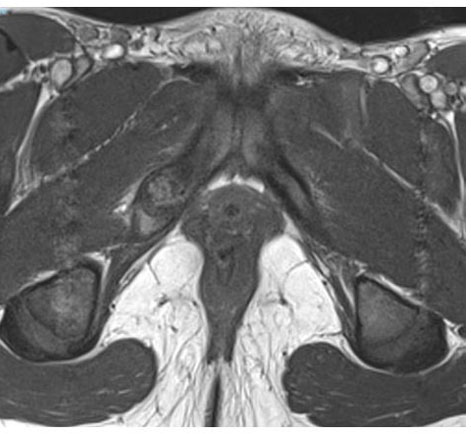

As described in the Wait et al. study [5], pelvic MRI performed on a whole-body 1.5 T scanner revealed hyperintense signal alteration of the bone marrow surrounding the right IPS on T2-weighted images, symmetrical enlargement of IPS, a transverse hypersignal band-like structure perpendicular to the pubic axis, a local collection, and marked edema of the surrounding soft tissues (Figure 4). These imaging findings, combined with clinical symptoms, were suggestive of acute osteomyelitis.

Figure 4: Pelvic MRI performed on a whole-body 1.5 T scanner reveals hyperintense signal alteration of the bone marrow surrounding the right ischiopubic synchondrosis on T2-weighted images, with symmetrical enlargement of the IPS. Additional findings include a transversal hypersignal band-like structure perpendicular to the pubic axis at the center of the right synchondrosis, a local collection, and marked edema of the surrounding soft tissues.

Share Image: